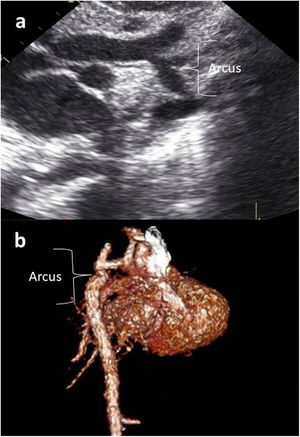

Images were reconstructed to 0.6 mm in thickness and to a reconstruction interval with a 25f kernel filter; they were processed on a separate workstation (Vitrea, Vital Images Inc., Minnetonka, MN) with multiplanar reformatting, maximum-intensity projection, and volume rendering (Figures 1 and 2). Multidetector CT images were prospectively reviewed by two radiologists with 15 (AT) and five (CT) years experience in cardiovascular imaging, and decisions were made by consensus.